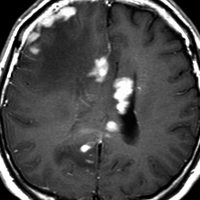

これは1990年代の古い例ですがリンパ腫の増大が早いことをお見せします。左側のはTHP-COPという化学療法をする前のものです。真ん中のは化学療法から4日目で,腫瘍は小さくなりました。でも,2コース目の化学療法の直前(4週間後)にもう一度MRIをしてみたらすごく大きくなっていました。この化学療法は効いているのだか効いていないのだか判らないことになります。化学療法を行なうならとても強い薬剤を使わなければなりませんし急がなければなりません。